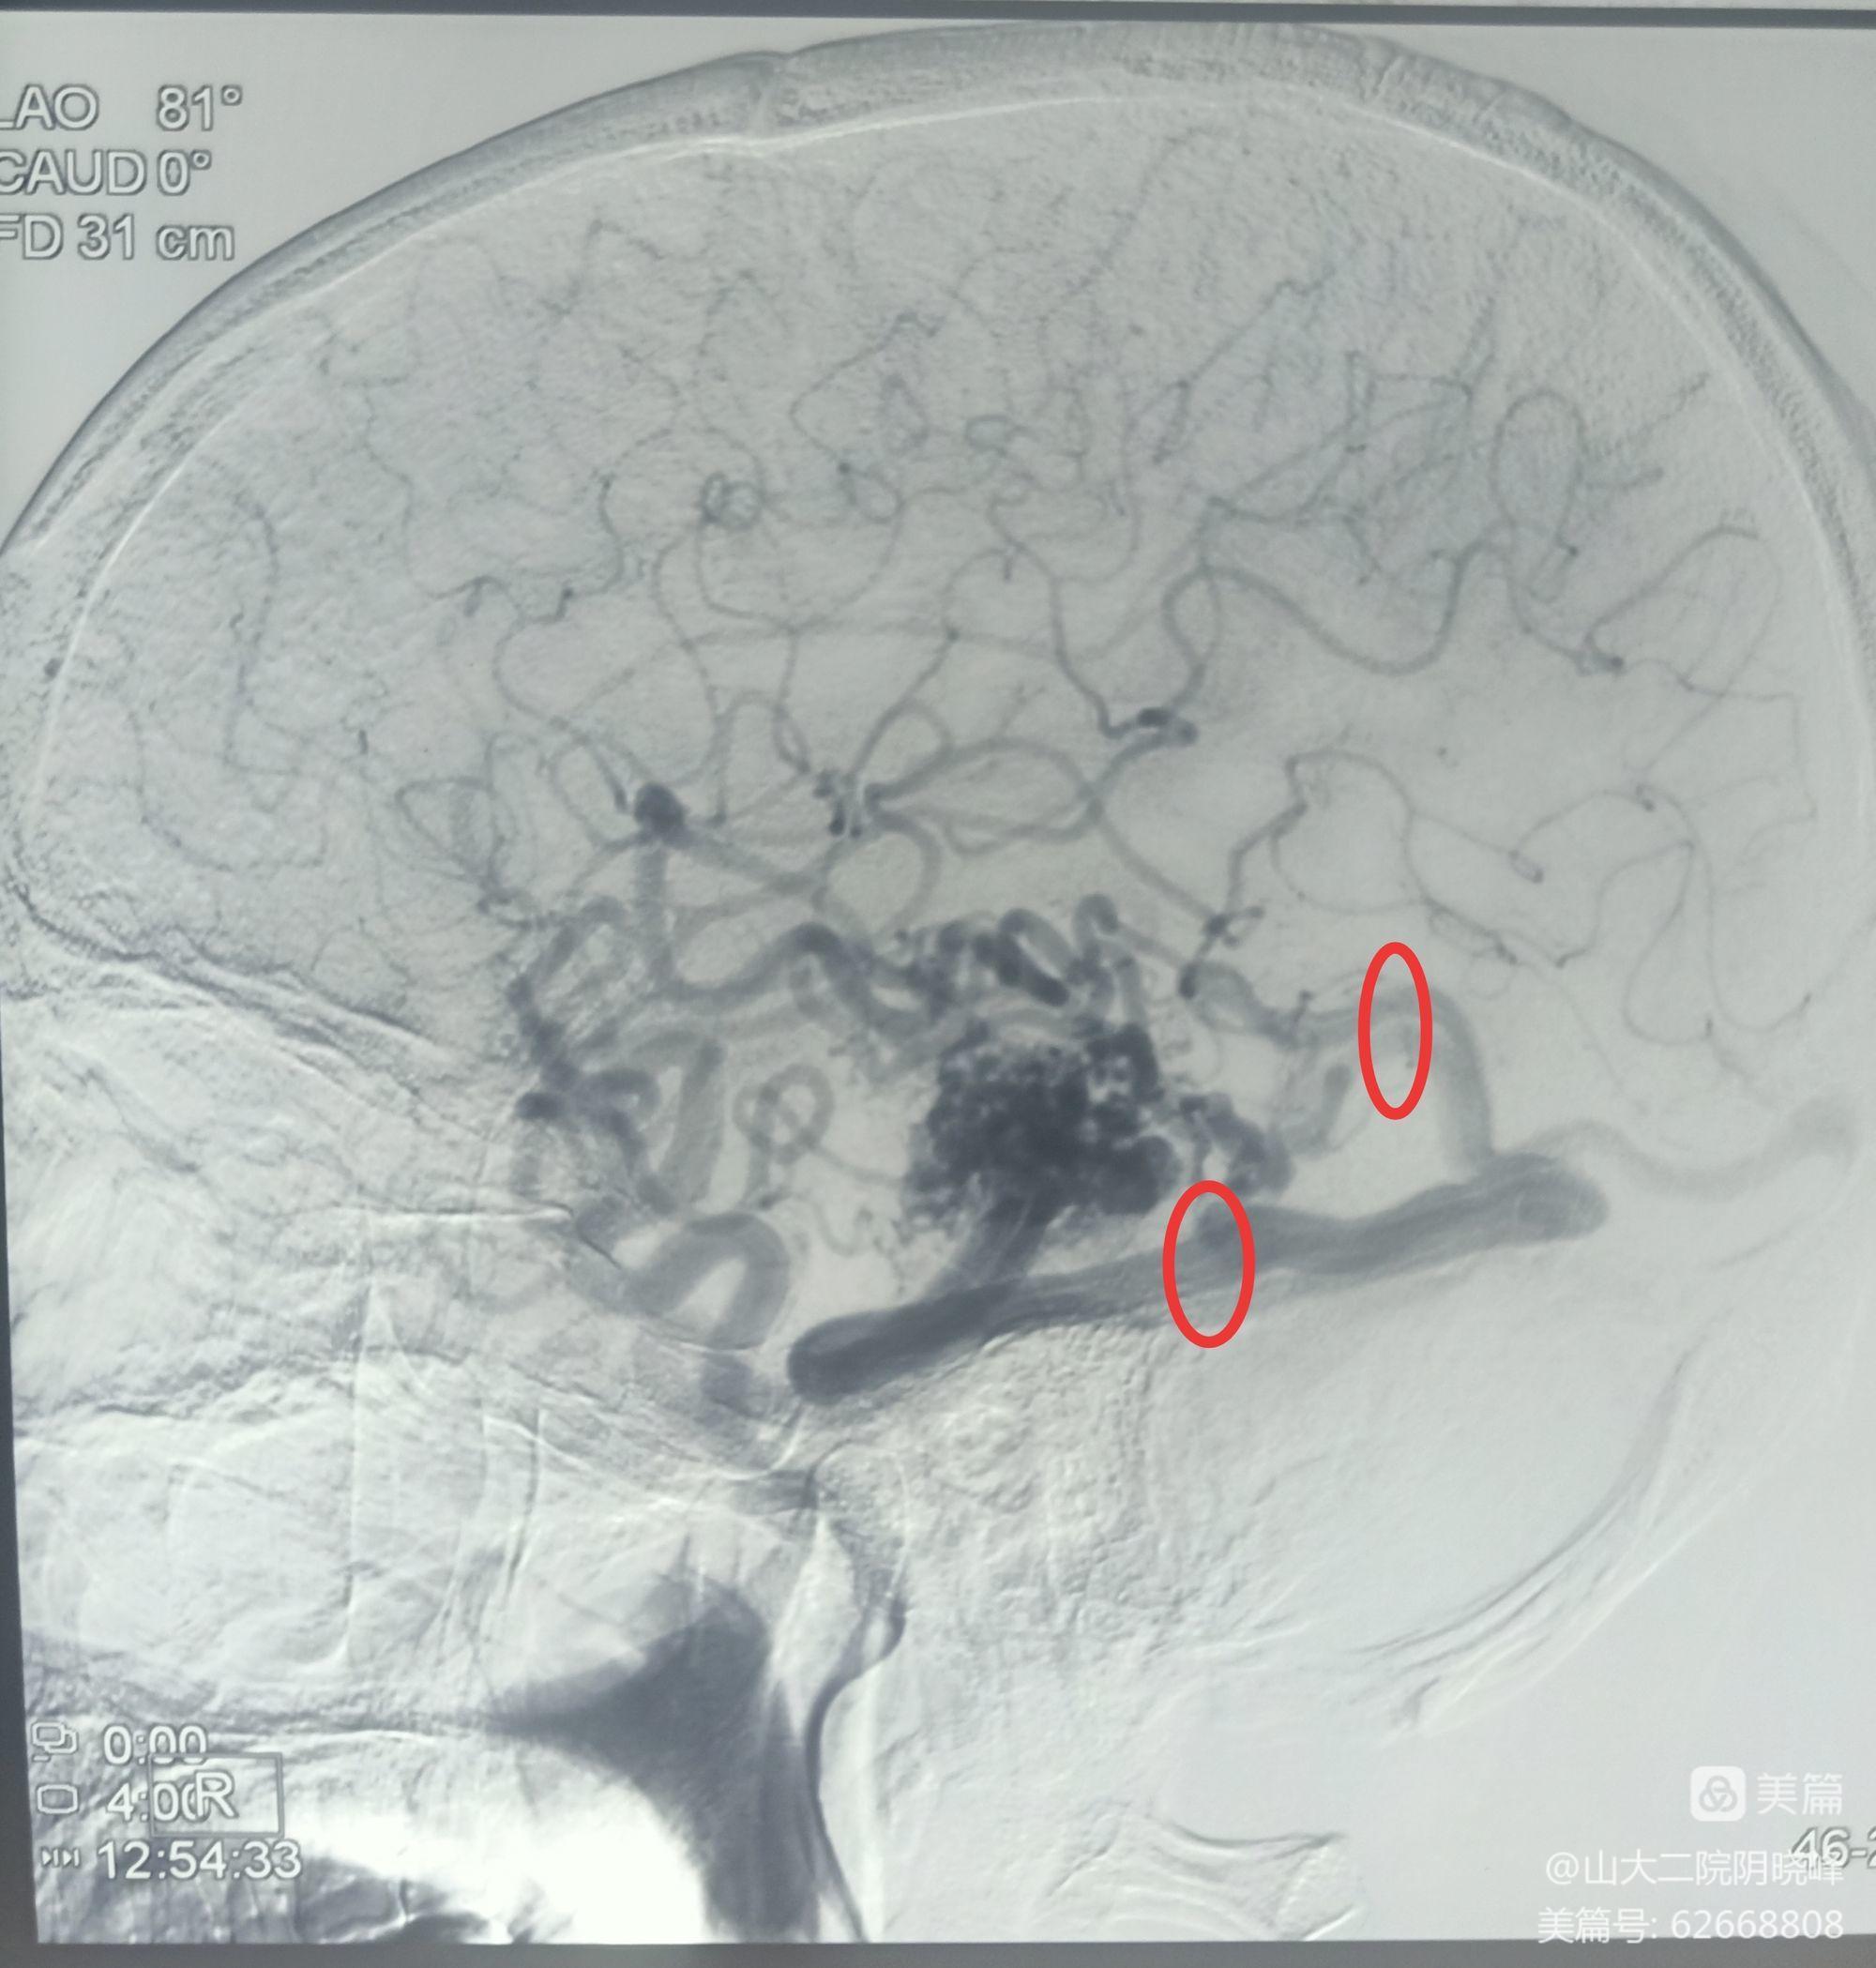

术前DSA明确供血动脉

术前DSA明确引流静脉

术前DSA

术中DSA复查造影:未见动静脉畸形显影,证实病灶全切。